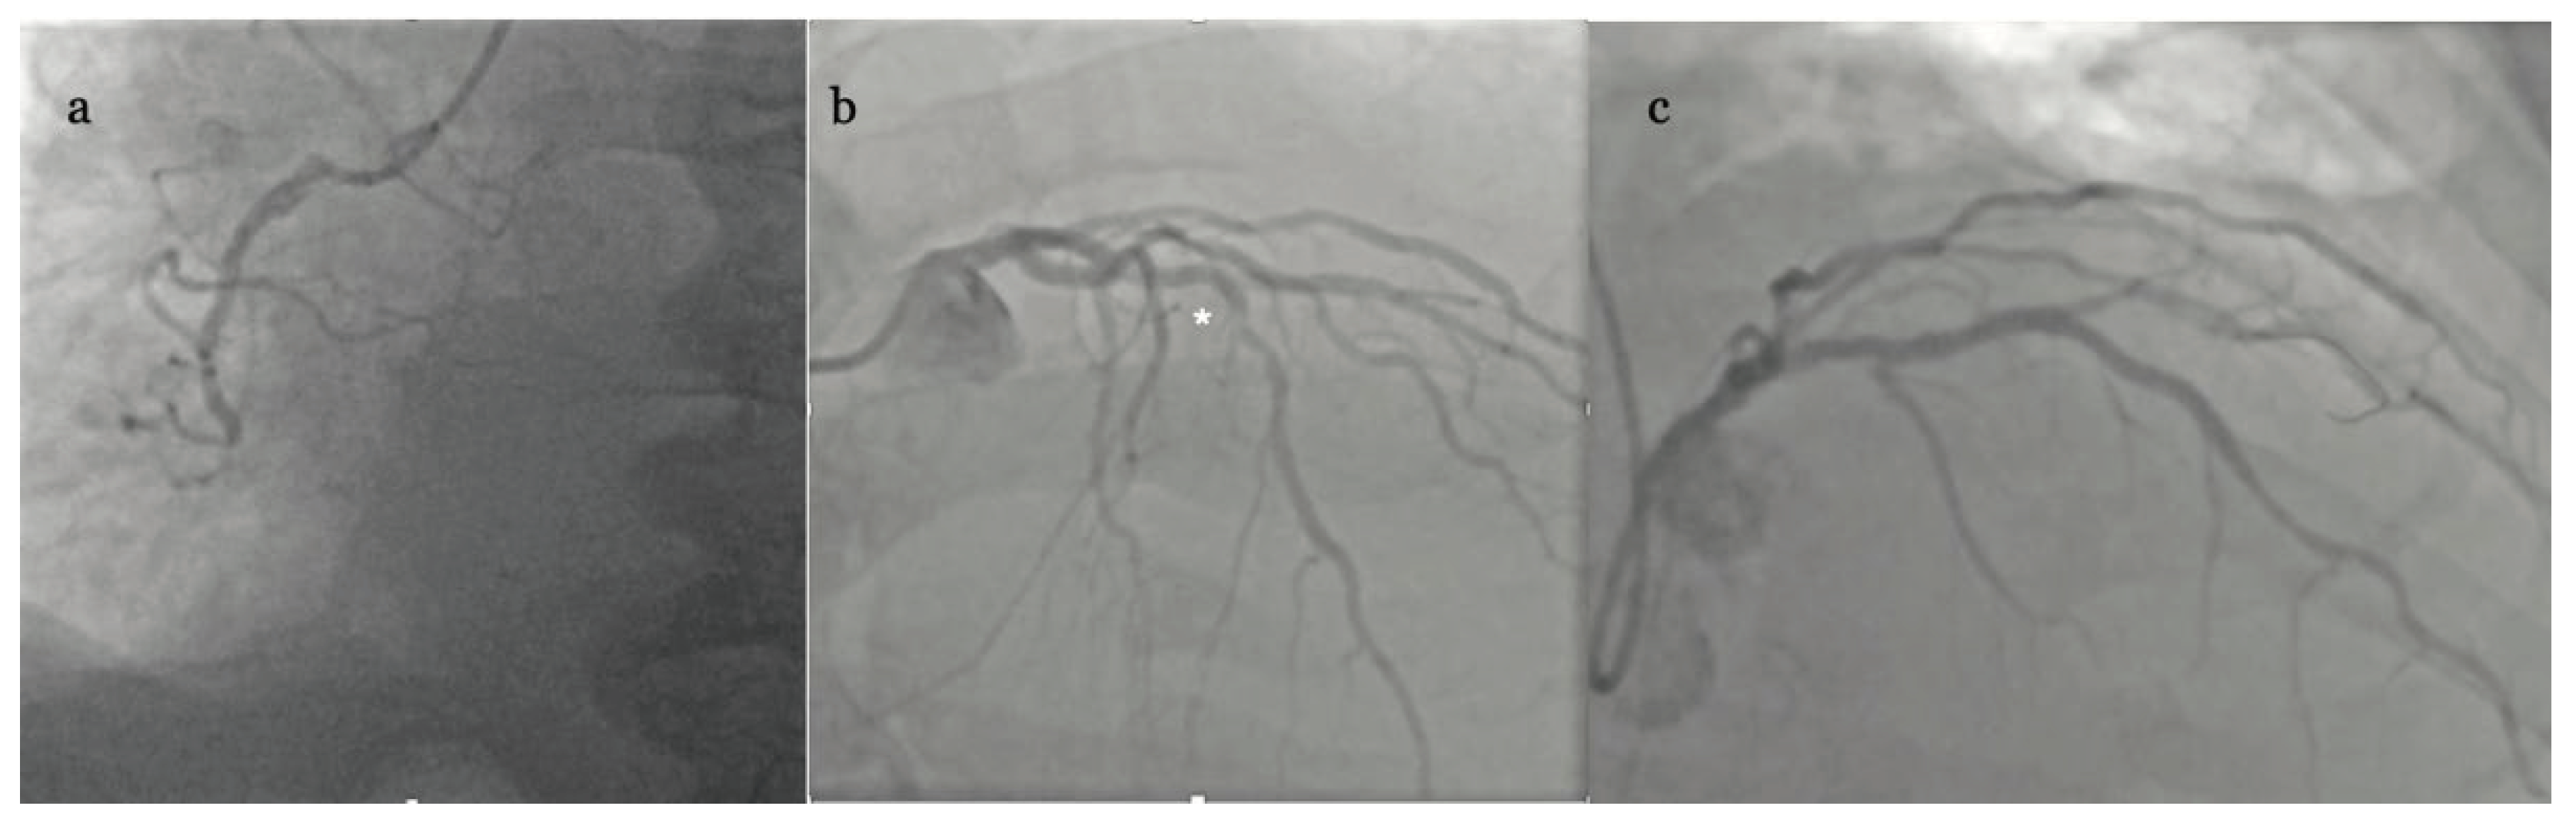

The patient was admitted to our invasive cardiology ward and sent for urgent coronary angiography (CAG) which revealed occlusion of right coronary artery (RCA) in 2nd segment without collateral circulation and significant stenosis in middle (7th) segment of left anterior descending artery (LAD) (Figure 3 a-b).

At this point the whole clinical picture indicated recent but sustained transmural myocardial infarction complicated by subacute left ventricular inferior free wall rupture (LVFWR) with subsequent formation of false aneurysm. No loading dose of P2Y12 inhibitors were given and there was no attempt at reopening of RCA (signs of necrosis on ECG and ECHO, no residual chest pain), instead urgent cardiosurgical consultation was requested. The decision was made to send the patient to reference cardiovascular surgery center (120 km apart) with the idea of definite repair (aneurism excision, left internal mammary bypass graft to LAD). The transport was uneventful and done by helicopter emergency medical service (HEMS). But the surgical team on-duty perceived the risk of open-heart surgery too high and instead performed only drainage of blood from pericardial sac (1300 cc) using substernal approach.

After intervention the patient was sent back to our institution, was hemodynamically stable and soon weaned from catecholamines but received antibiotics due to Staphylococcus aureus surgical-site infection. On 10th postoperative day cardiac computer tomography (CT) was done which showed residual 7 mm of fluid and inferior wall aneurysm of 54 x 82 x 29 mm with only 2,5 mm wall thickness. We asked for Heart Team Consultation pointing again for the need of aneurismectomy, but the decision was made to recommend percutaneous coronary intervention (PCI) of LAD and observe the clinical status of the patient. Accordingly, PCI was performed (18 days from acute presentation) with one drug eluting stent (DES) implantation to mid LAD under intravascular ultrasound (IVUS) guidance with optimal result (Figure 3c). The patient was discharged home in stable condition on clopidogrel and apixaban, guideline directed heart failure medical therapy as well as on amiodarone treatment due to persisting runs of non-sustained VT (nsVT) on ECG (Figure 4).

Figure 3. Coronary angiography examination showing (a) mid right coronary artery (RCA) occlusion, (b) significant left anterior descending artery (LAD)* stenosis, and (c) result of drug eluting stent (DES 3,0 x 36 mm) implantation to mid LAD.